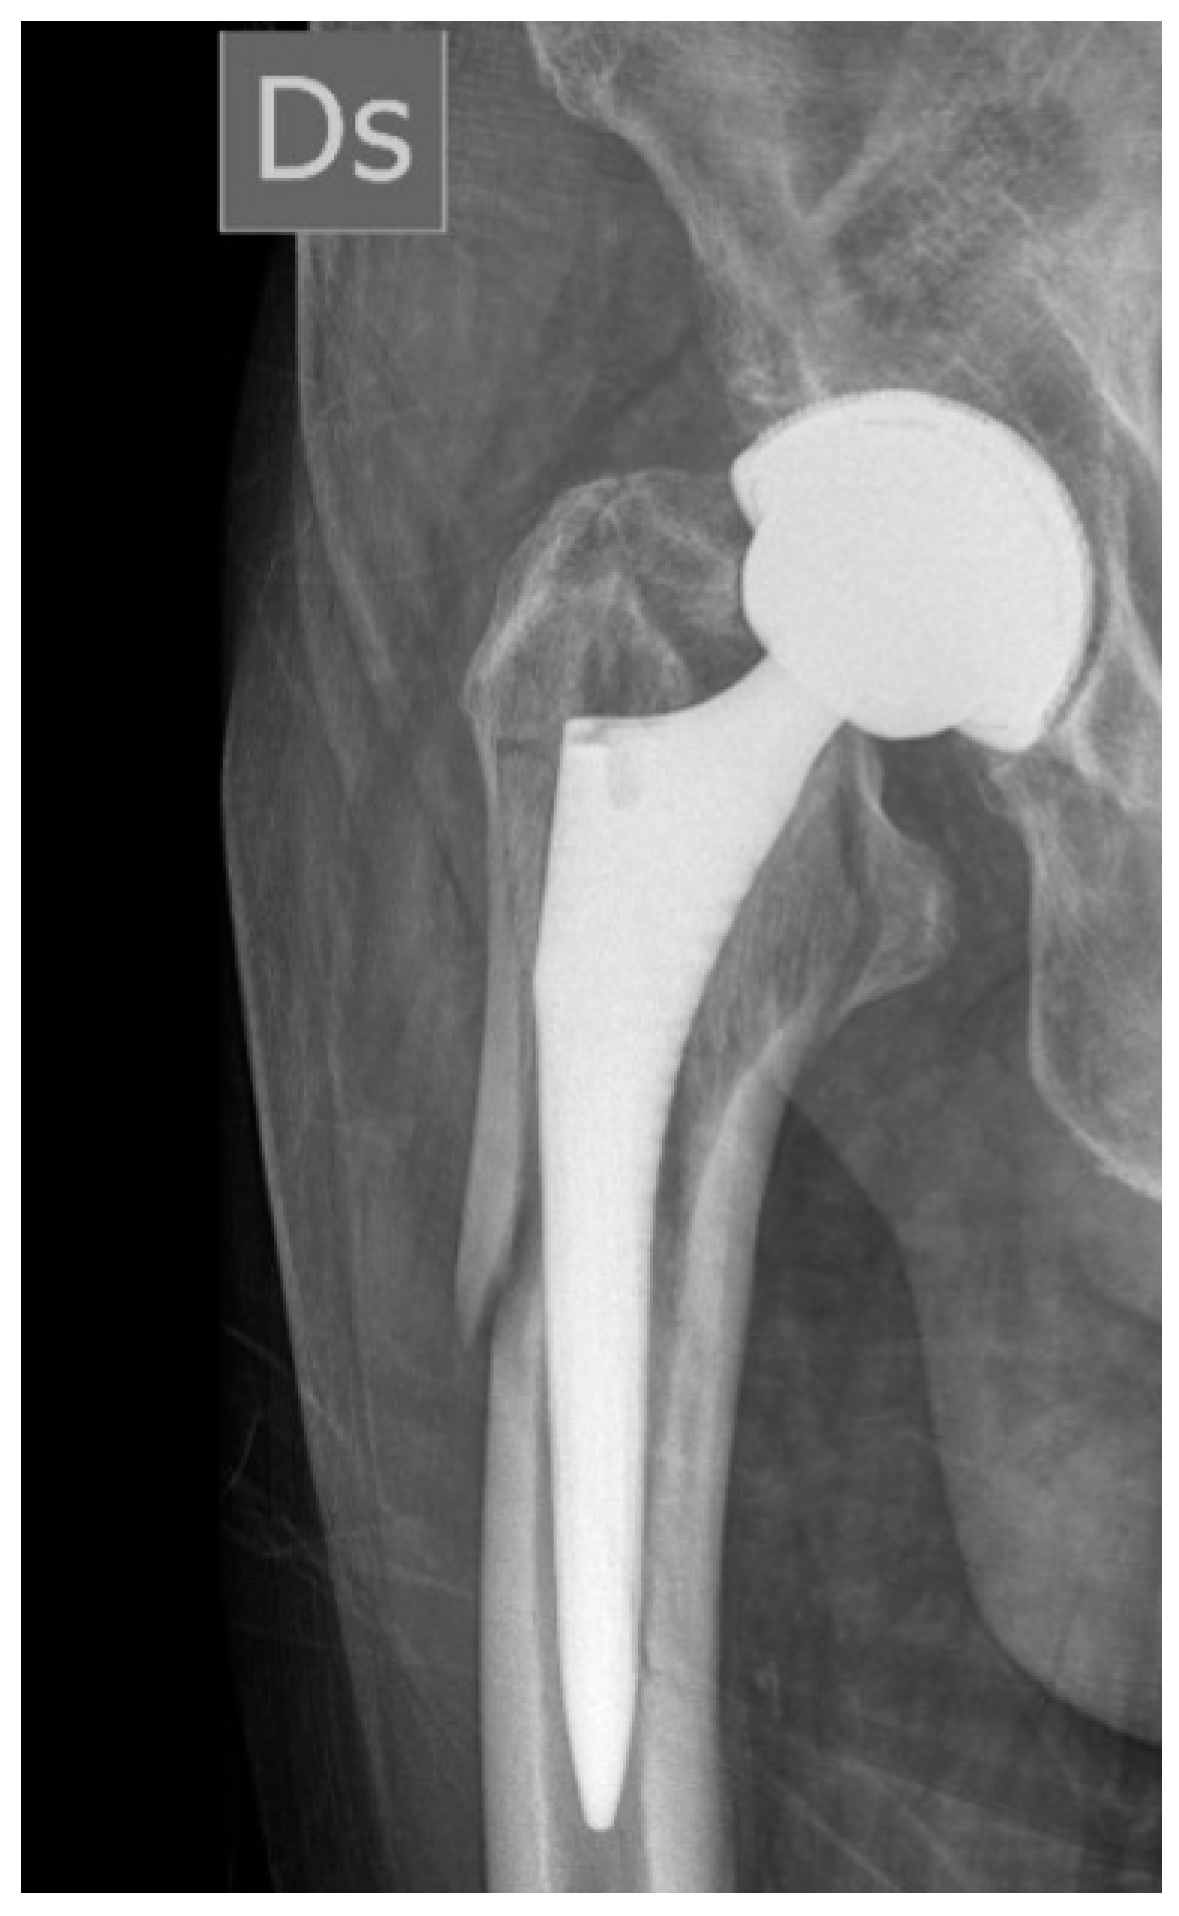

1.1. Surgical Technique

3. Results